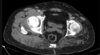

Osteoma Osteóide - A TC mostra o nidus radioluscente, cercado por reação esclerótica e , as vezes, pode mostrar um ponto esclerótico dentro do nidus.

Predomina 10 - 30 anos.

Nicho radiotransparente < 1cm circundado por reação esclerótica. Localização cortical / justacortical em ossos longos: femur proximal e tibia.

Clinica tipica: dor mais intensa a noite aliviada por AAS.

Quando nidus > 2cm = osteoblastoma. TC é a modalidade de escolha (RM pode não ver o nidus).